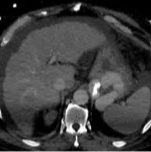

脉冲电场促使细胞膜产生缺陷 细胞内稳态的丧失导致细胞死亡(细胞凋亡++) 周围结构(血管、胆管、热敏感器官……)的保护措施 不存在“散热效应(heat sink effect)” 对于无法切除且不适合常规热消融治疗的肝脏肿瘤的治疗方案 对肝细胞癌(HCC)经 IRE 治疗后长期预后的回顾性评估 ![]() 来自两家三级医疗机构长达 12 年使用IRE的真实案例经验 IRE 治疗 HCC的局部疗效、安全性以及长期肿瘤学结果的评估 主要目标: 单独使用内镜下射频消融术后的局部肿瘤进展率 次要结局指标: 所纳入标准 肝细胞癌的诊断(依据欧洲肝脏学会标准或通过组织学确认) 最大肿瘤直径≤5 厘米 在首次的内镜射频消融手术中, 最多可治疗 3 个肿瘤。 BCLC 0 期、A 期或 B 期 排除标准 浸润型肝细胞癌伴血管或胆管侵犯 肝移植术后肝细胞癌的复发有类型的复发

超声(CT/磁共振/Carm-CT) + 虚拟靶点透视显示

插入 3 至 6 根电极 对于肿瘤直径小于 3 厘米,无接触式操作 最大电极间距为 25 毫米 心脏同步化和去极化(curarization)